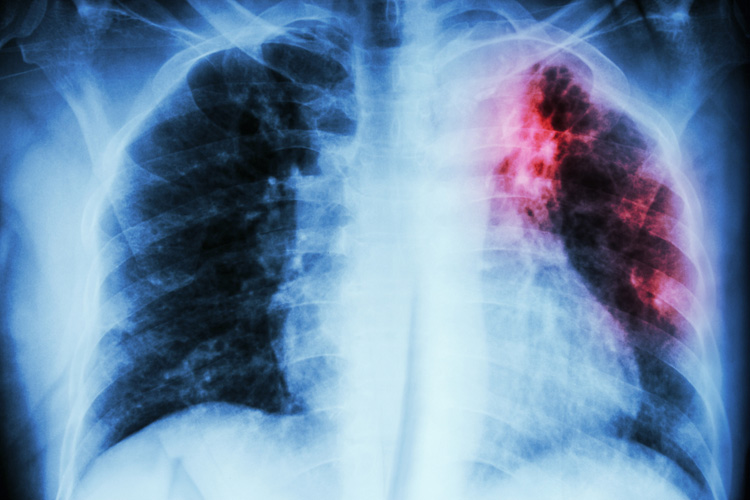

Туберкулез является распространенной инфекционной болезнью, вызываемой различными видами микобактерий. Болезнь распространяется преимущественно воздушно-капельным путем, чаще всего поражая легкие. Если туберкулез не лечить, то один пациент с активной формой заболевания в среднем способен заразить 10-15 человек в год. Туберкулез является одной из главных причин смерти в мире. По данным за 2016 год, в минувшем году в мире туберкулезом заболели более 10 млн человек, 1,7 млн человек в 2016-м умерли от этой болезни. В том числе заболели более 1 млн детей и погибли 250 тысяч малышей.

Туберкулез легких –инфекционное заболевание, причиной которого выступает туберкулезная палочка (также известная как палочка Коха) – агрессивный и устойчивый микроб. Для данного заболевания характерно образование очагов специфического воспаления в пораженных тканях, а также выраженная общая реакция организма. Палочка Коха способна на протяжении длительного времени выживать в почве, на поверхности загрязненных предметов, высохшей мокроте и является устойчивой ко многим средствам дезинфекции.

Довольно часто туберкулез легких протекает без видимых симптомов и может быть обнаружен случайно, например, при прохождении флюорографии. Одними из первых симптомов заболевания являются: слабость, снижение веса, ухудшение сна, повышенное потоотделение, снижение аппетита, головокружение, повышенная температура тела (около 37 градусов), увеличение групп лимфоузлов. Если на данном этапе заболевания не обратиться за медицинской помощью, то со временем к вышеперечисленным симптомам добавятся: кашель с выделением мокроты, отдышка, боли в грудной клетке, выделение крови при кашле. Последние два симптома являются признаком сложной формы заболевания и требуют незамедлительного лечения.

Несмотря на экспресс-тесты на туберкулез, на сегодняшний день ведущую роль в диагностике туберкулеза играют классические методы: обнаружение палочки Коха в посеве мокроты больного, гистологическая идентификация микобактерий в мазках и рентгеноскопия очагов поражения.